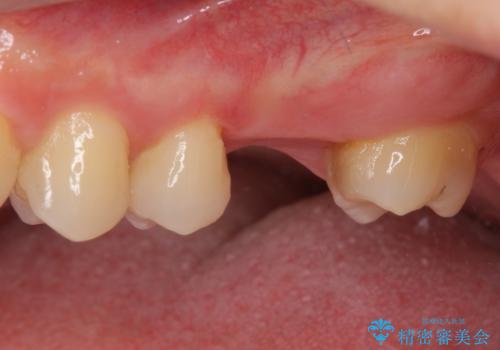

- 前歯のクロスバイトと、大学生のころから放置している虫歯を気にして来院された患者様です。

マウスピースでの矯正治療を希望されていましたが、前歯のクロスバイトは不十分な仕上がりや歯髄壊死などのリスクが高くなるため、術前にワイヤーで大まかに整えてからインビザラインにて矯正治療を行うこととしました。

奥歯の虫歯は抜歯が必要であったので、矯正治療前に抜歯をし、矯正治療と並行してインプラントによる補綴治療を行うこととしました。